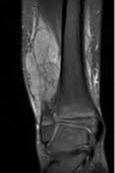

Se usa una amplia gama de técnicas de adquisición de imágenes para poder ver dentro del cuerpo y determinar el alcance de un sarcoma óseo y establecer la presencia o ausencia de enfermedad metastásica distante.

1. Rayos X

2. Resonancia magnética

3. TAC contrastado

4. Gammagrafía Ósea